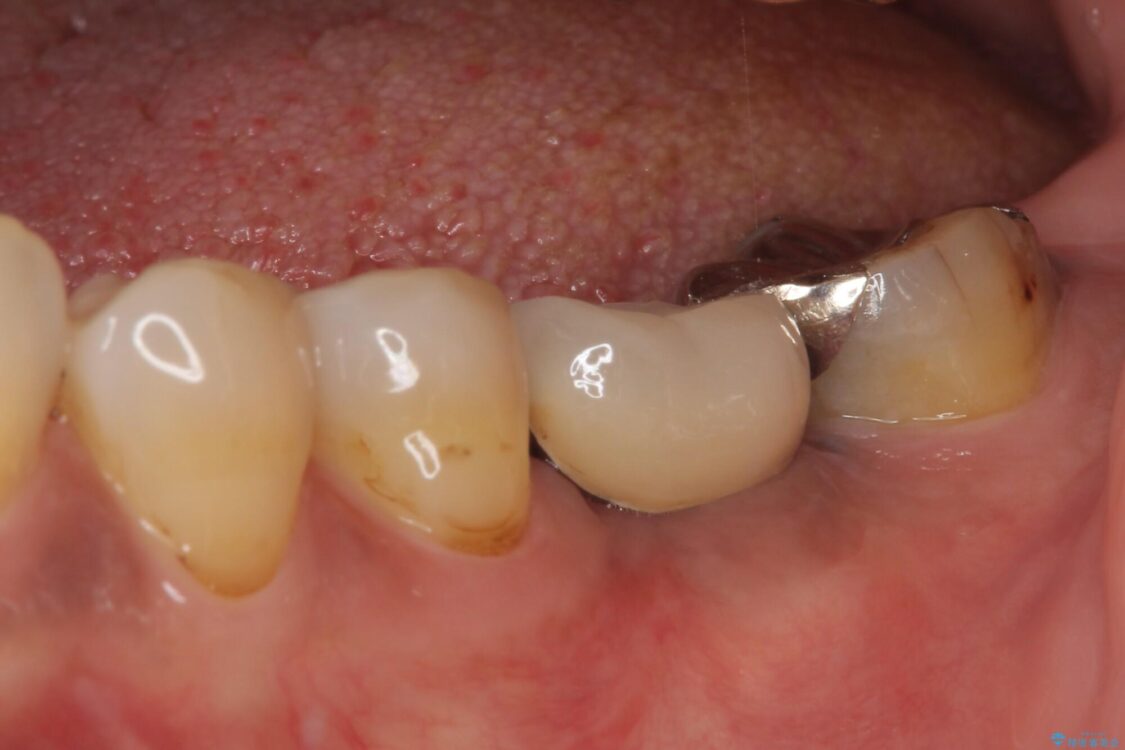

仮歯に変えた時点でしみる症状はなくなり、オールセラミッククラウンはまるで自分自身の歯のような舌触りとなり、大変満足していただきました。

• しみる奥歯 オールセラミッククラウンによる補綴治療 治療後画像